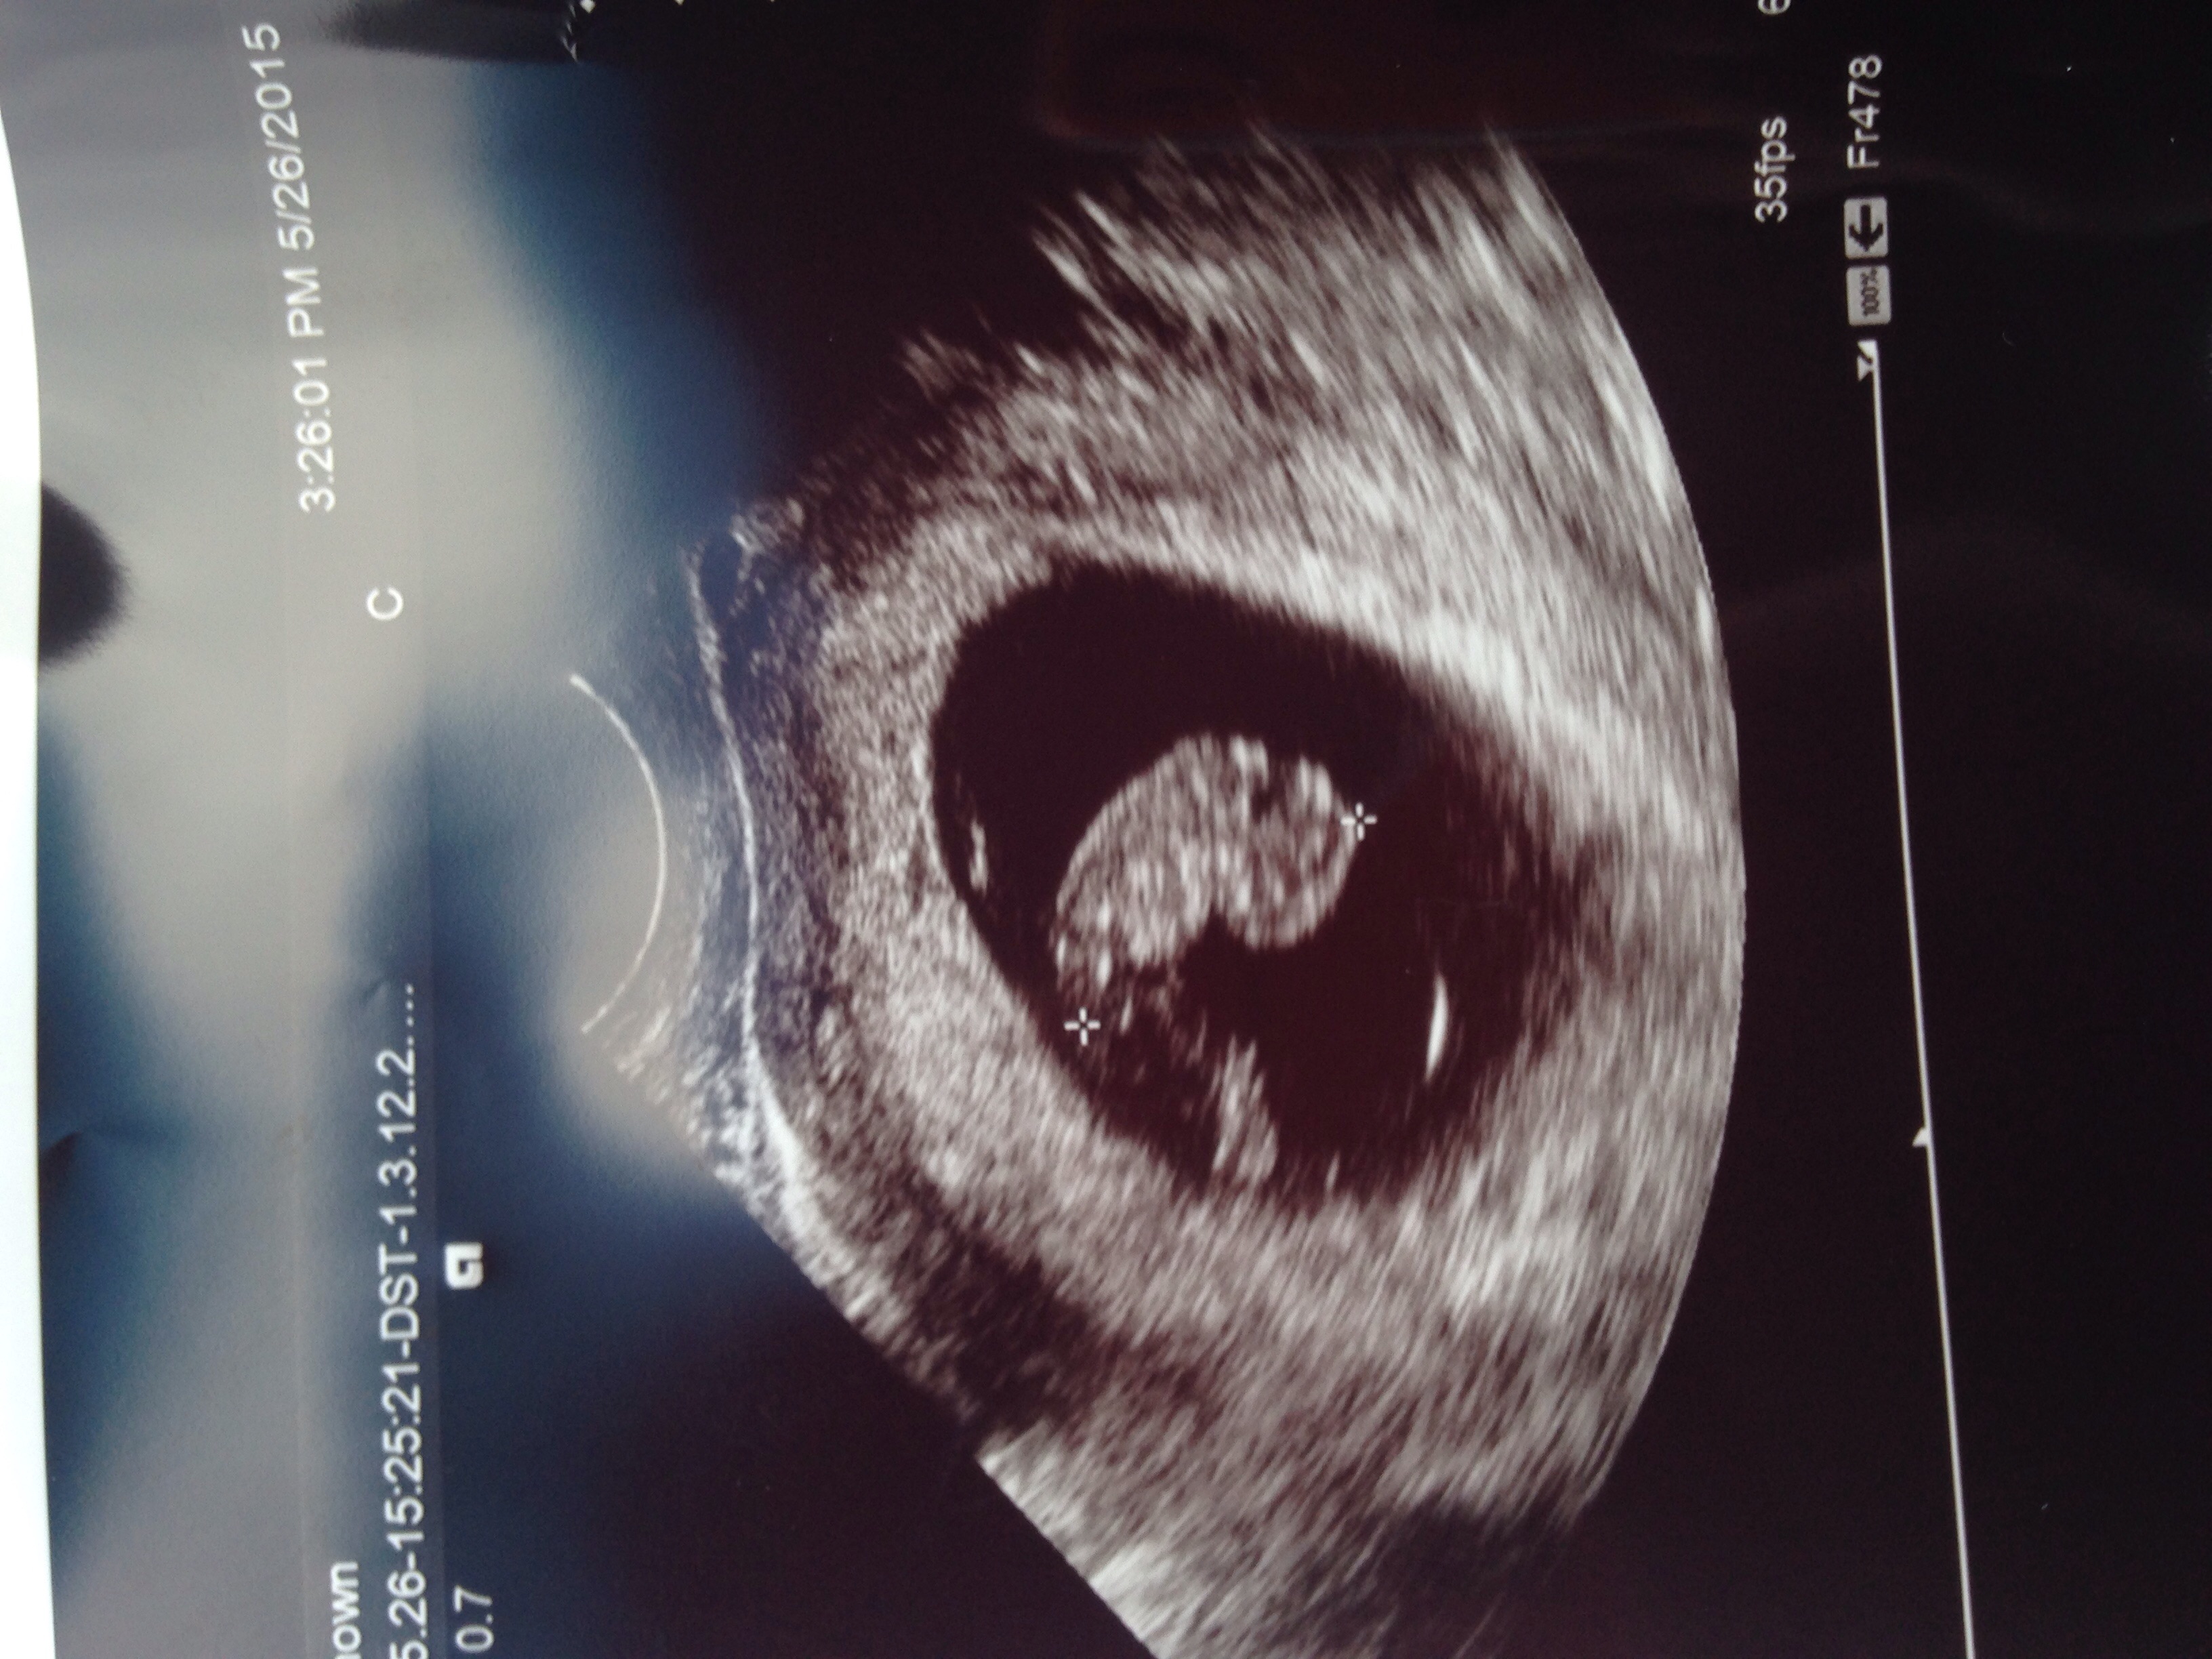

This is my transvaginal ultrasound. Baby is in the middle but you can see placenta forming on the left which indicates a girl. Still don't know if it's accurate